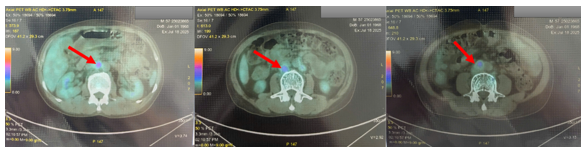

Chụp cắt lớp phát xạ positron PET/CT:

1. Hình ảnh vài hạch thượng đòn trái (SUVmax: 2.85), nhiều hạch ổ bụng (SUVmax: 4.89), hạch chậu hai bên (SUVmax: 4.66) tăng chuyển hóa FDG tương ứng với hạch ác tính. Đối chiếu với mô bệnh học, hóa mô miễn dịch.

2. Hình ảnh tổn thương khuyết xương ở thân đốt sống L4, xương chậu phải, xương mu phải, tăng chuyển hóa FDG khả năng ác tính (SUVmax: 3.08).

3. Hình ảnh tăng chuyển hóa FDG ở amidam bên phải (SUVmax: 3.71) Đối chiếu với nội soi.

4. Hình ảnh nốt giảm tỷ trọng ở nhu mô gan hạ phân thùy IV, tăng nhẹ chuyển hóa FDG (SUVmax: 2.76). Cần phối hợp đánh giá thêm.

5. Hình ảnh vài nốt mờ dưới màng phổi và sát rãnh liên thùy ở thùy dưới phổi phải và thùy trên phổi trái, không tăng chuyển hóa FDG. Nên lưu ý bệnh lý viêm. (Đối chiếu với CT scanner lồng ngực: phù hợp với hình ảnh)

Hình 1. Hình ảnh PET/CT toàn thân của bệnh nhân.

Hình 3. Hình ảnh nhiều hạch ổ bụng (SUVmax: 4.89) tăng chuyển hóa FDG tương ứng với hạch ác tính (mũi tên đỏ). Đối chiếu với mô bệnh học, hóa mô miễn dịch.